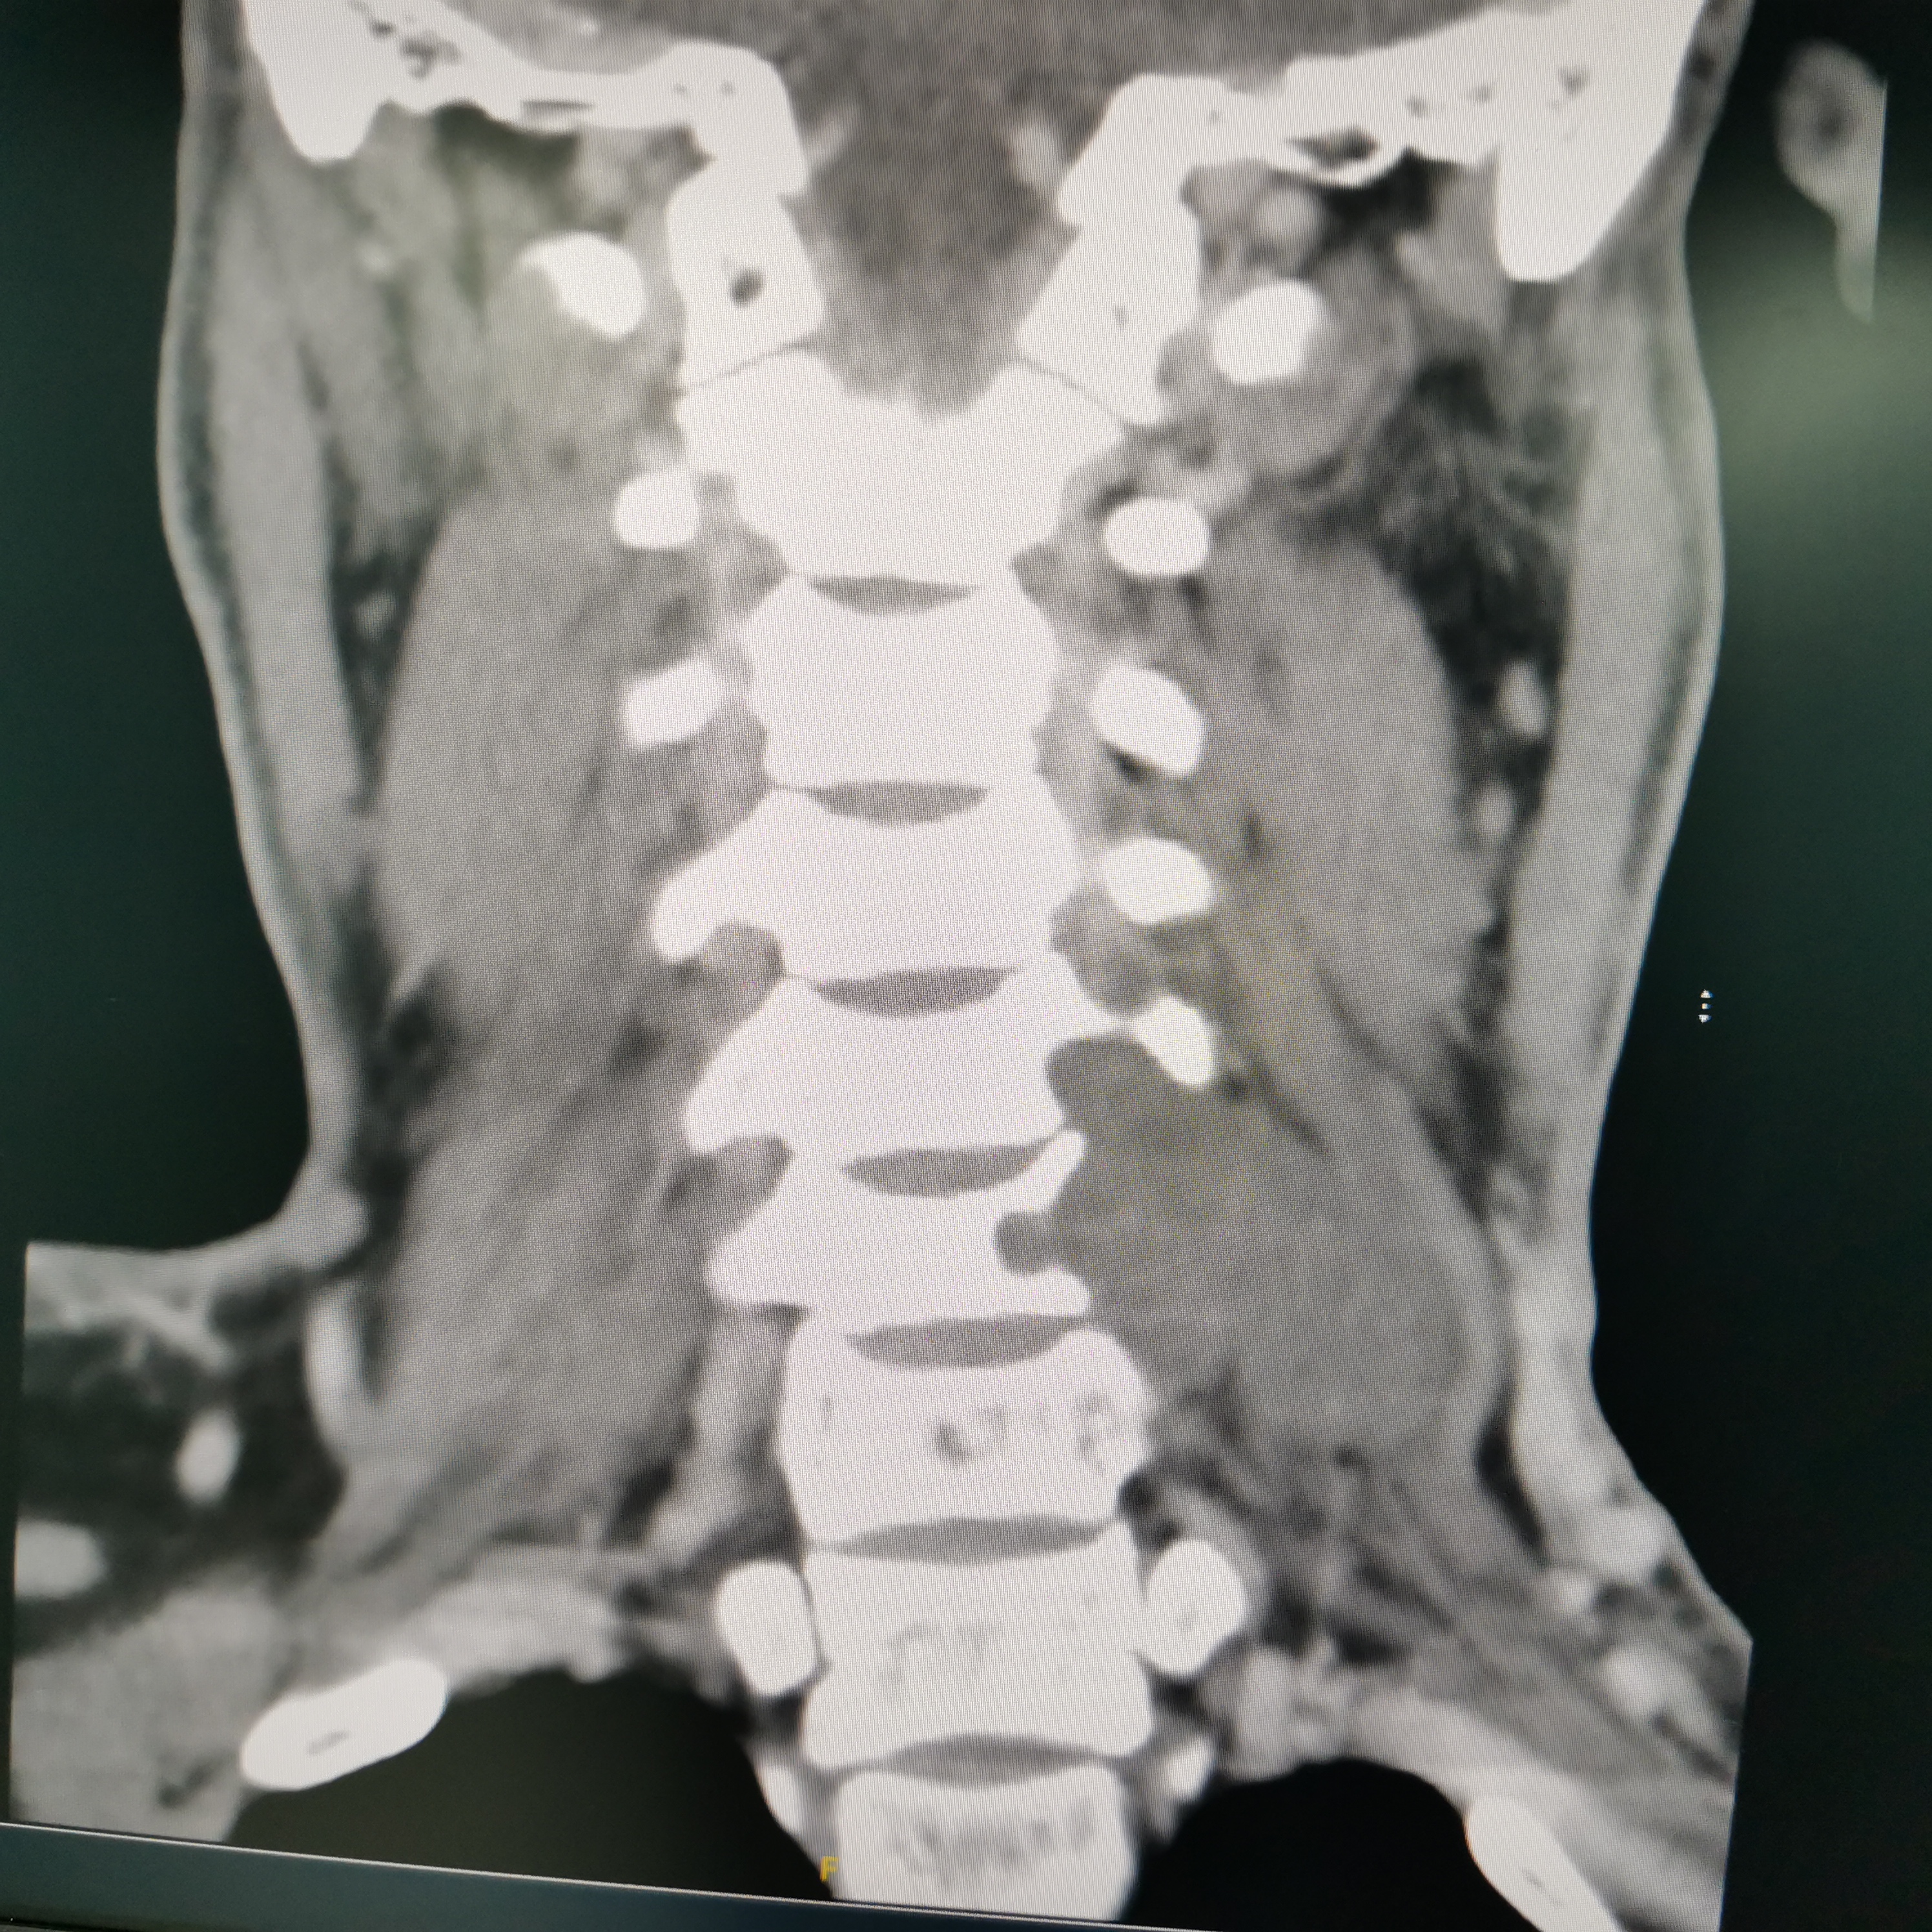

颈椎哑铃型神经纤维瘤,椎间孔汇合,安全又便于操作~